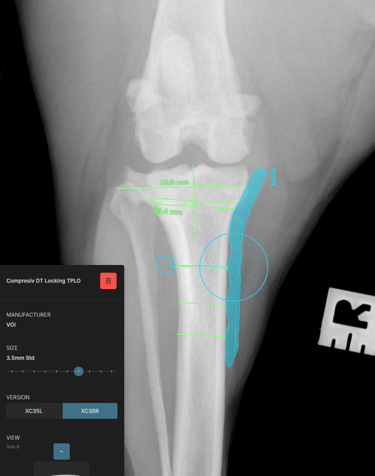

The surgical plan was developed using specialized veterinary orthopedic planning software, which allowed for precise measurements and implant selection, ensuring optimal execution of the surgical procedure (Figs. 3 and 4).

Preoperative measurements indicated a tibial plateau angle (TPA) of 25°. A TPLO saw blade size 24 was used, achieving a rotation of 8.3 mm. Pre-surgical measurements were: A = 11 mm, B = 13 mm, and C = 35 mm.

A 3.5 mm TPLO locking plate was placed with two compression screws. A 2 mm anti-rotational pin was left in situ, as it did not interfere with the placement of the proximal fragment screws.

Fig. 3